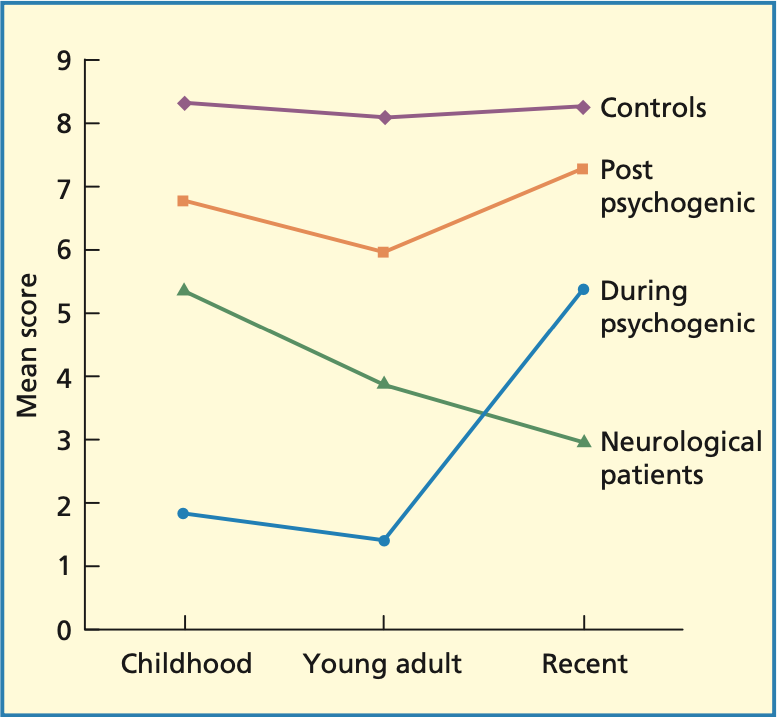

Autobiografisches Gedächtnisinterview

Persönliches semantisches Gedächtnis

Spezifität und Informationsgehalt von persönlichen Erinnerung

Ribots Gesetz

Bei einer retrograden Amnesie bleiben ältere Erinnerungen eher erhalten als jüngere Erinnerungen

Psychogene Amnesie: jüngere Erinnerungen bleiben eher erhalten als ältere Erinnerungen